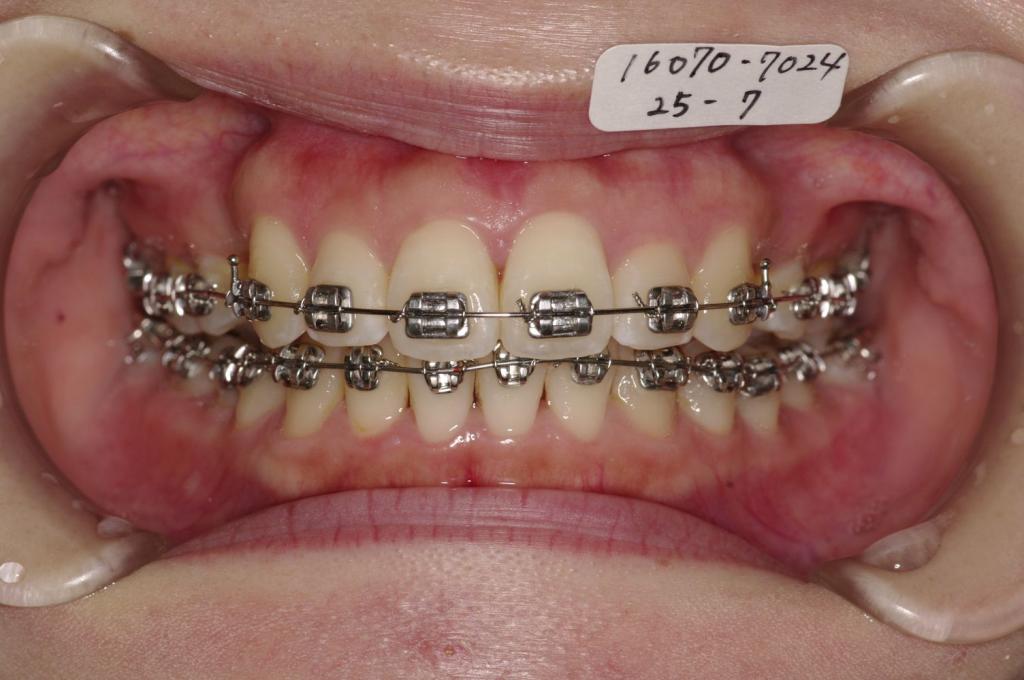

- 前歯、出っ歯・開咬の矯正治療

- 前歯が出ている